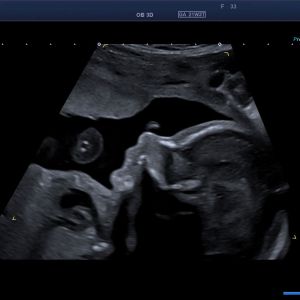

Beurteilt werden Aussehen und Funktion aller sichtbaren Organe des Ungeborenen und weitere Faktoren wie Wachstum, Fruchtwassermenge, Blutfluss in der Nabelschnur, Lage und Aussehen des Mutterkuchens (Plazenta) sowie dessen Durchblutung. Die 3D/4D-Darstellung kann bei bestimmten Fragestellungen ergänzende Informationen liefern.